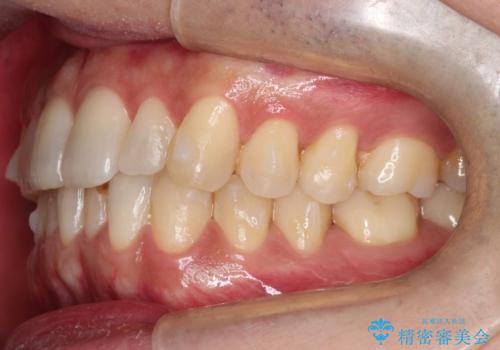

- 前歯の歯並びの改善を希望され来院された患者様です。

初診時の歯並びの状態としては、下顎に中等度のがたつき(叢生)がある状態でした。

抜歯は行わず下顎の奥のスペースを利用して歯をスライドする方法の他に親知らずの抜歯そして上下ともに歯列弓の拡大やディスキング(歯と歯の間の隙間を作る処置)を行い叢生を改善しました。

歯の大きさの不揃いが原因の正中のズレは、ディスキング量を調整することで合わせました。

矯正装置としてはマウスピースを使用しています。